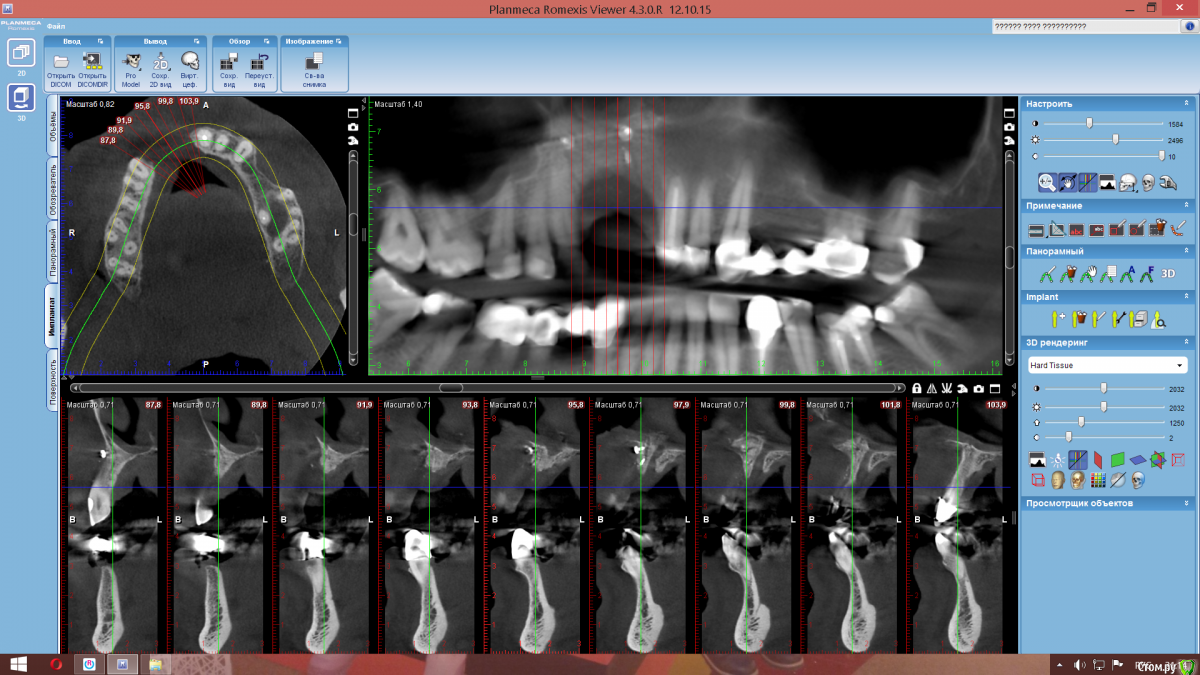

Nazim_NV86 Опубликовано 3 апреля, 2017 Поделиться Опубликовано 3 апреля, 2017 Доброе время суток коллеги. Вот такой вот вертикальный дефект. Была неудачная попытка костной пластики. Собираюсь делать ламинами, но хотел бы почитать ваши рекомендации, а возможно и ссылки на похожие операции. Ссылка на комментарий

kamranchick Опубликовано 4 апреля, 2017 Поделиться Опубликовано 4 апреля, 2017 Доброе время суток коллеги. Вот такой вот вертикальный дефект. Была неудачная попытка костной пластики. Собираюсь делать ламинами, но хотел бы почитать ваши рекомендации, а возможно и ссылки на похожие операции. Ссылка на комментарий